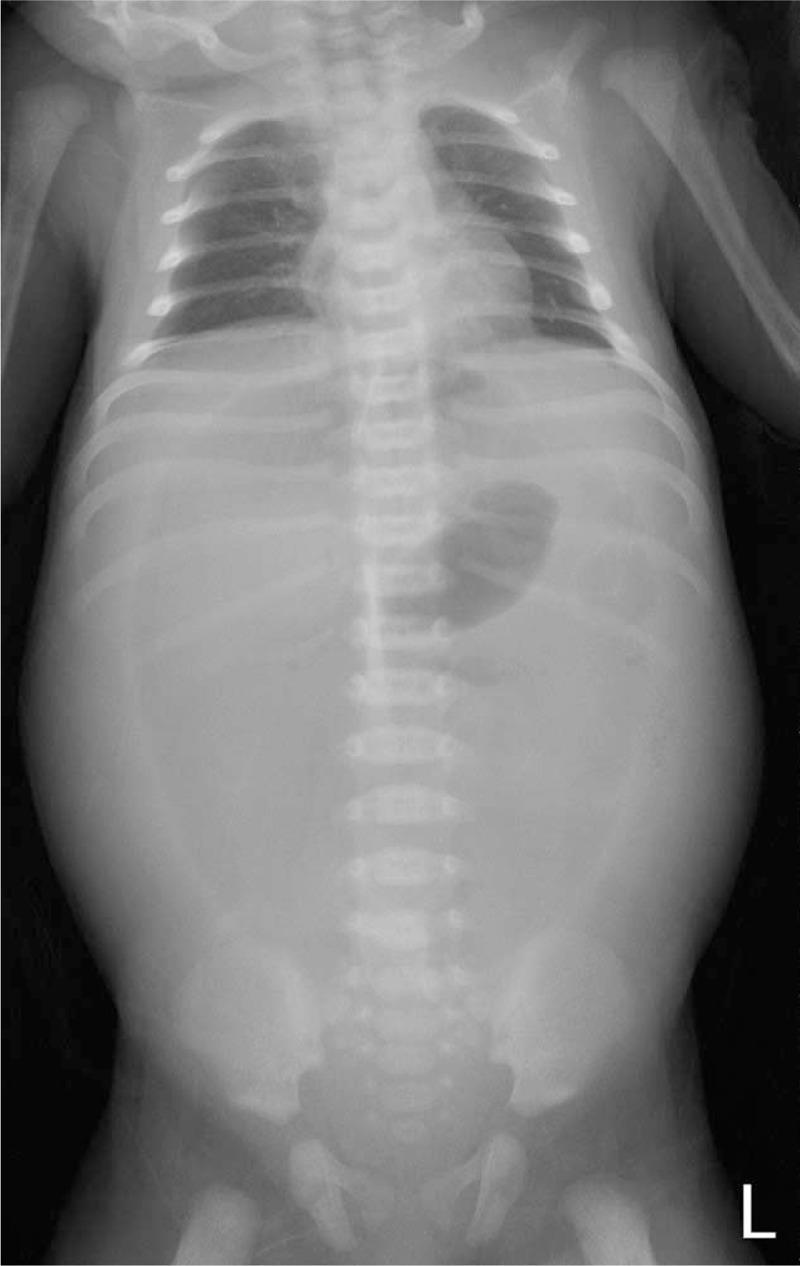

Two neonates received a diagnosis of gastric perforation based on clinical presentation and imaging studies. The 2 patients underwent emergent surgery, which yielded favorable outcomes.

两名新生儿根据临床表现和影像学检查被诊断为胃穿孔。这两名患者接受了急诊手术,结果良好。